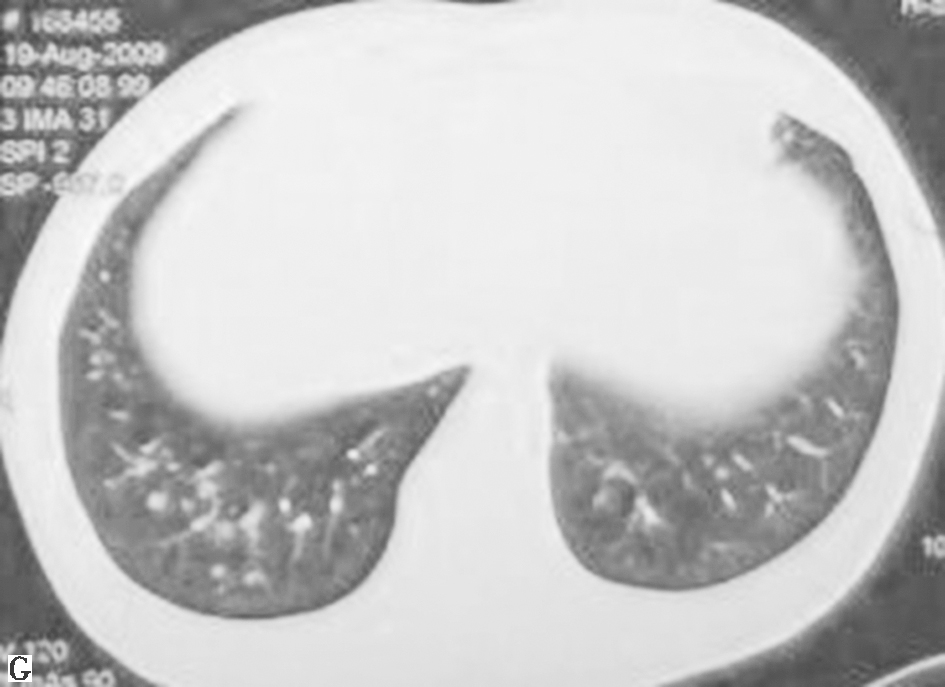

鉴于患者临床症状不重,无肺外系统受累,建议患者严格戒烟(包括被动吸烟)。患者在严格戒烟1个月后,症状逐渐减轻;3个月后复查胸部CT见双肺结节及空洞明显减少(图3);严格戒烟6个月后复查胸部CT显示双肺散在微小结节进一步减轻、减少(图4)。

图3严格戒烟3个月后复查胸部CT表现